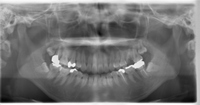

武蔵野市の歯科健診ではレントゲン検査を行うことが出来ます。

レントゲン検査では

①根の先の状態(根尖病巣:こんせんびょうそう)

②上顎洞の状態

③歯周病の状態

④虫歯

⑤親知らずの状態

⑥唾石(だせき)

⑦アゴの骨の状態

など、直接口の中を診ただけではわからない事が発見できます。

レントゲン撮影することで圧倒的に情報量が多くなります。